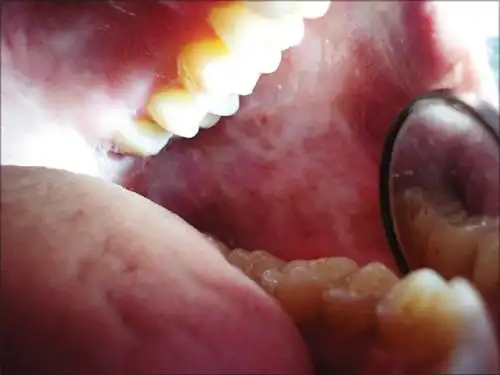

口腔黏膜纤维化